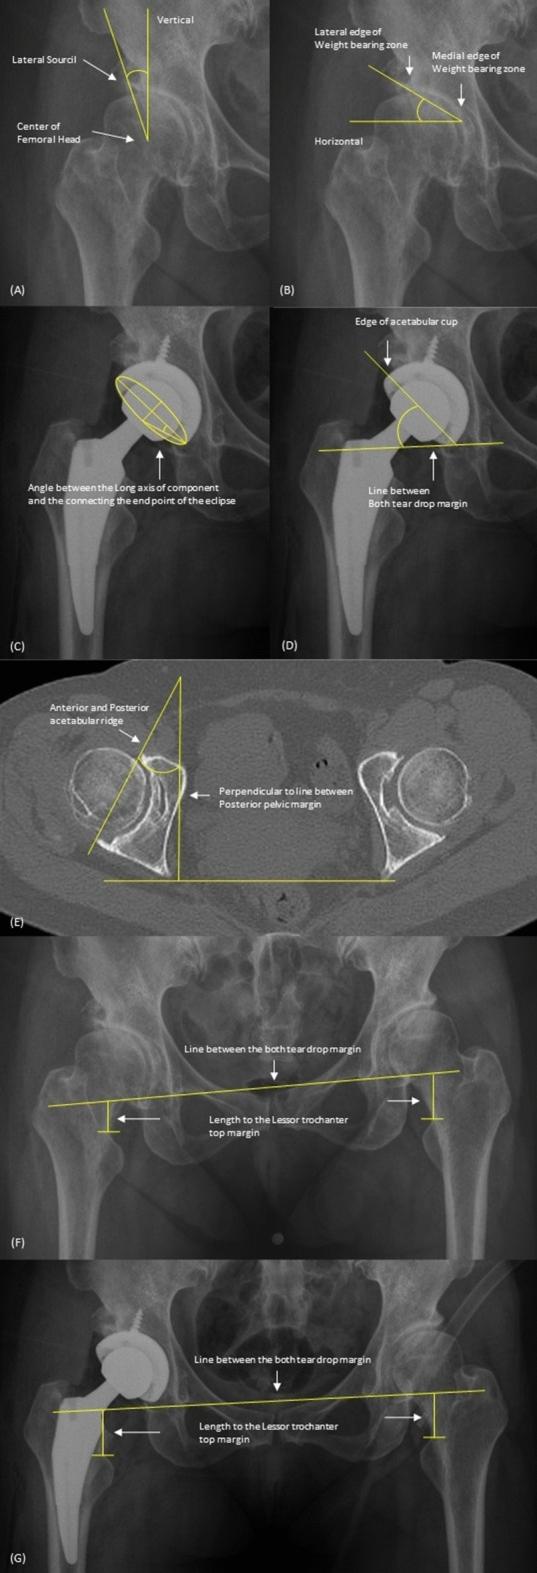

Total hip replacement arthroplasty (THA) in hip dysplasia patients has a higher dislocation rate than in patients with simple hip osteoarthritis due to anatomical deformation. Therefore, to reduce postoperative THA dislocation is the challenge for arthroplasty surgeons. From 2015 to 2020, 1525 patients underwent THA performed by two surgeons at a single institution. A total of 152 patients involving 172 THAs were included. The patients were classified into dual-mobility (DM) and fixed-bearing (FB) acetabular cup groups. The occurrence of postoperative dislocation and functional evaluation of the hip joint, was analyzed before and after surgery using the modified Harris hip score(mHHS). There was no difference in the preoperative demographics and radiographic parameters between the groups. The incidence of postoperative hip dislocation was significantly lower in the DM group (DM 0% vs. FB 9.0%) (P value = 0.003). The mHHS showed no difference before surgery and after surgery (DM 91.80 vs FB 92.03). Treating hip dysplasia patients with THA using a dual-mobility acetabular cup can reduce postoperative dislocations, and could be used for the better management of these patients.

全髋关节置换术(THA)在髋关节发育不良患者中的脱位率高于单纯髋关节骨关节炎患者,这是由于解剖变形所致。因此,降低术后 THA 脱位是关节置换外科医生面临的挑战。2015 年至 2020 年,有 1525 名患者在一家机构接受了两位外科医生的 THA 手术。共纳入 152 名患者,涉及 172 例 THA。将患者分为双动(DM)和固定衬垫(FB)髋臼杯组。使用改良 Harris 髋关节评分(mHHS)评估术前和术后术后脱位的发生和髋关节功能。两组患者的术前人口统计学和影像学参数无差异。DM 组术后髋关节脱位发生率明显低于 FB 组(DM 0%比 FB 9.0%)(P 值=0.003)。mHHS 在术前和术后无差异(DM 91.80 比 FB 92.03)。对于髋关节发育不良患者,使用双动髋臼杯进行 THA 治疗可降低术后脱位率,可更好地管理这些患者。